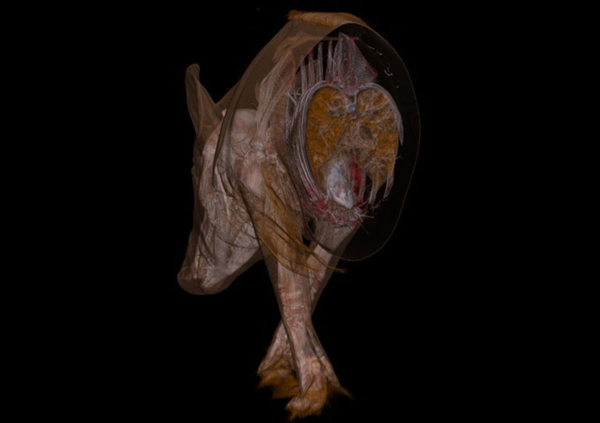

在随后的幻灯片中,您将看到来自瑞典医学图像科学与可视化中心(the Center for Medical ImageScience and Visualization ,CMIV)的Anders Persson和他的同事们运用CT,MRI和超声得到的令人惊叹的尸检图片。这些图片描绘了人体骨骼,消化道,循环系统和大脑以及野猪的前端结构。

10,动物,横切;骨骼和脏器位置清晰可见。